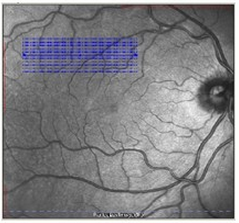

二、唯一具有Eye-Tracking实时主动动眼追踪技术的OCT——“所见即所得”Eye-Tracking动眼追踪技术可以消除扫描伪迹,避免检查出现漏诊和误诊,并具有*好的重复性

Eye-Tracking动眼追踪技术衍生出TruTrackTM技术,实现随诊时精确同一位置,为精确量化评价疾病进展和治疗效果变化提供了可能——PDT和抗VEGF治疗疗效评估金标准

医生可在各个浏览终端根据cSLO图像自定义设置OCT扫描模式,按需进行OCT扫描

七、唯一具有个性化扫描方式的OCT

可以自定义扫描方式

可以实现任意区域扫描

医生可以根据病情进行个性化扫描,节约检查时间,提高临床效率